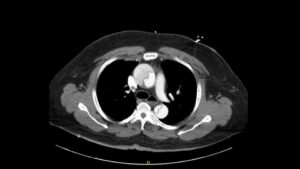

Aortic Dissection Involving the Aortic Root, Left Common Carotid Artery, and Iliac Arteries Images. CT Unannotated Axial 2. JETem 2022